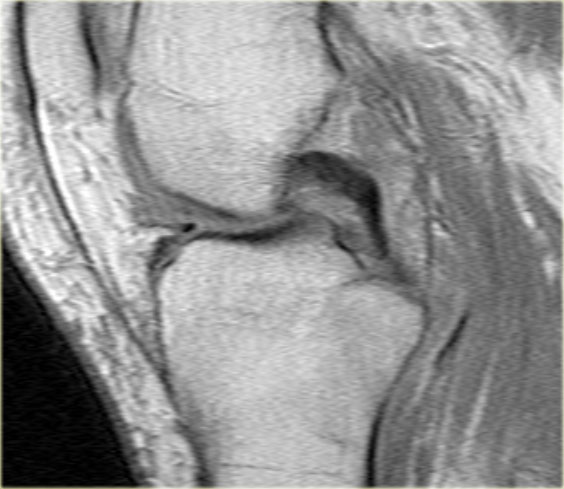

Cùng ca bệnh trên với hình ảnh mặt phẳng sagittal.

Lưu ý phần bị rách của sụn chêm chạy ra phía trước qua hố gian lồi cầu (các mũi tên)

- Thông thường chỉ có hai cấu trúc chạy trong hố gian lồi cầu. Ở đây chúng ta thấy dây chằng chéo sau bình thường.

- Dây chằng chéo trước bình thường.

- Phần bị rách của sừng sau như là ‘cấu trúc thứ ba’

trong hố gian lồi cầu. - Phần bị rách chạy ra phía trước.

- Phần bị rách nhập vào sừng trước và giả tạo hình ảnh rách dọc ở sừng trước.

Lưu ý phần còn lại nhỏ của sừng sau.